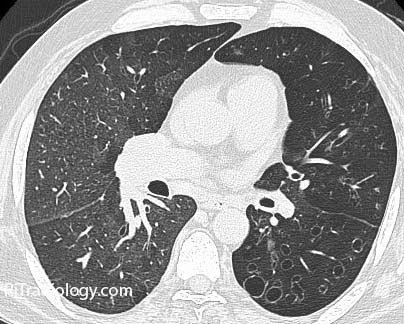

Swyer-James syndrome - эмфизема легких, при которой обычно поражается только одно легкое; болезнь чаще всего начинается в детстве или в юности. Развивается после перенесенного некротического бронхита и, по мнению специалистов, вероятнее всего, ее причиной является присутствующий в организме вирус.